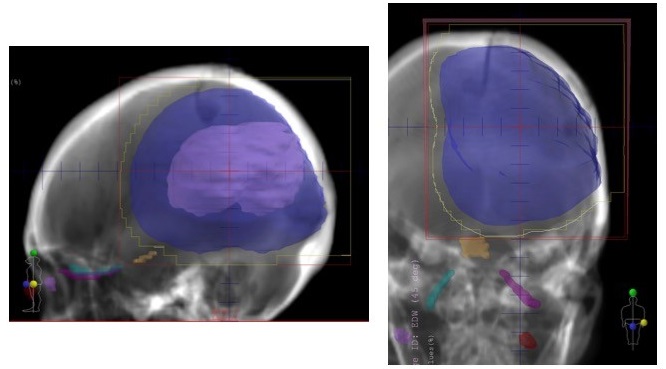

主としてリニアック(またはライナック、直線加速器)と呼ばれる装置で、X線を発生させ病変を照射する方法で、もっとも一般的な放射線治療装置です。病変周囲の正常な組織の影響を抑えるため、少ない量を週5日、数週間かけて照射します。転移性脳腫瘍に対する全脳照射や悪性神経膠腫に対する治療などに用いられています。強度変調放射線治療(IMRT)や容積強度変調回転照射(VMAT)とよばれる照射方法によって、病変の形状に合わせて照射範囲や放射線量などを調節できるようになりました。

図 左頭頂葉悪性神経膠腫術後に対する放射線治療